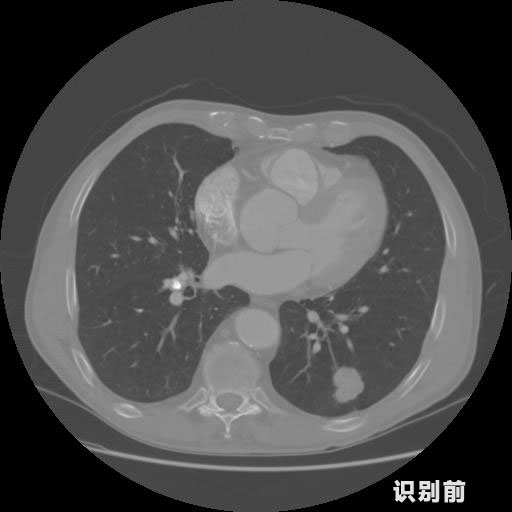

英特健康A(chǔ)I深度學(xué)習(xí)醫(yī)療圖像識(shí)別系統(tǒng)案例_胸部CT

1.發(fā)現(xiàn)肺結(jié)節(jié)的可能性為95.56%---位于框指數(shù)位置:[331.70554 366.13406 365.21707 403.96234]